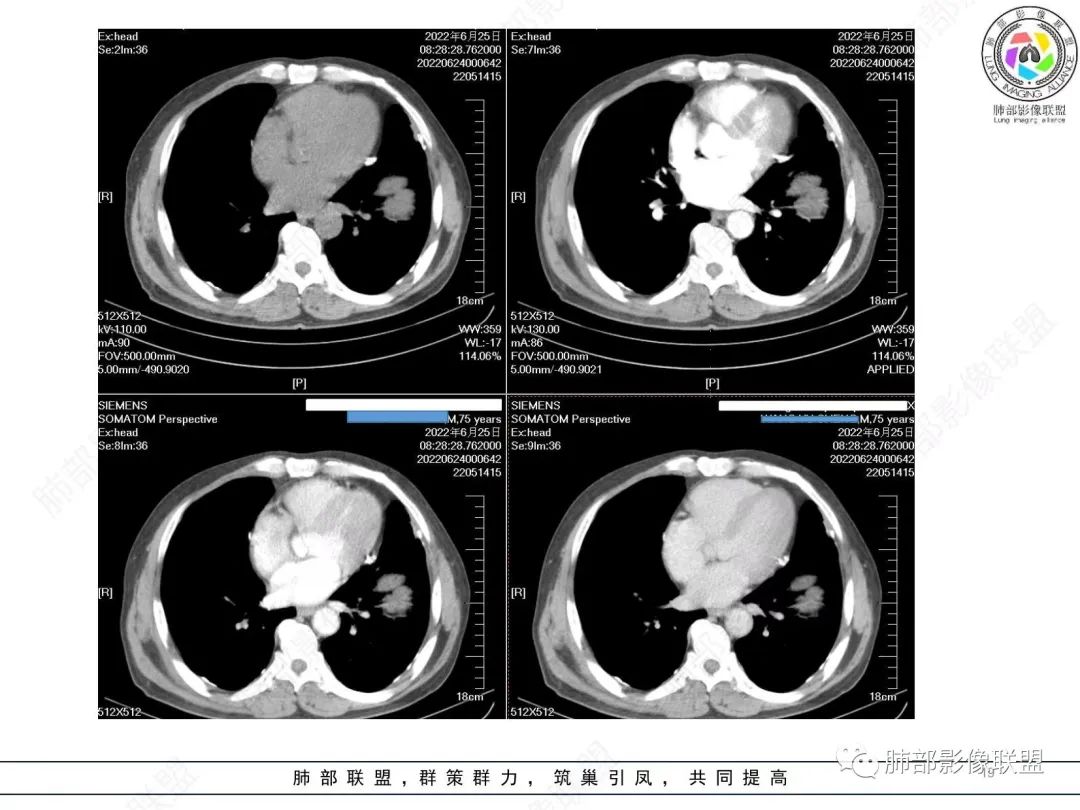

糖尿病史,慢性病程,左肺巨大肿块,跨叶生长,肿块近端可见充气支气管征及悬浮气泡,轻度圴匀强化,病变长轴与胸膜平行,炎性标志物正常,考虑放线菌,其次淋巴瘤

我要修正一下观点了:仔细看了视频,肿块占位效应明显,对周围血管,支气管有推挤,增强后强化不明显,NSE增高,半年体重下降25公斤,虽然有内部支气管扩张,血管漂浮,边界清楚支持淋巴瘤,但强化太低,膨隆,占位推挤太明显(淋巴瘤一般没有这么明显的占位效应),胸膜关系有载桩,恶病质明显(乏力,半年体重下降了25公斤),NSE也明显增高,就不支持淋巴瘤了。还是考虑外朝内的恶性肿瘤,间质来源的肉瘤伴有神经内分泌分化或者大神泌。

不支持淋巴瘤的有四点:1、对周围血管支气管推挤明显。2、胸膜有栽桩,3、强化太弱(淋巴瘤一般还是中度以上甚至高度强化多见),4、NSE升高明显,体重下降太明显。

腺癌一般不会有这么明显的推挤作用的。

淋巴瘤,鉴别间叶来源肿瘤或者神经内分泌肿瘤

支气管不像淋巴瘤,肺动脉走也不连续。支气管是断断续续的堵塞和扩张,狭窄。不是那种扩张

老年男性,糖尿病病史,消瘦、乏力三个月,肿瘤标志物高。左肺上叶胸膜下肿块,边界清晰,可见支气管影及坏死区,增强病灶边缘强化,内部未见明显强化,邻近胸膜有累及,考虑恶性,建议穿刺活检。

左肺紧贴胸膜巨大肿块,跨叶裂生长,密度均匀,边缘清晰,内支气管略扩张,增强见血管影,强化不明显,胸膜栽赃,钙化,考虑淋巴瘤。

我再建一下血管。支气管进入,但是近端推移,堵塞

大肿块,边缘光滑,深分叶

近端支气管堵塞、推移为主

部分类似于脐凹征

内部支气管扩张

肺动脉推移为主,边缘部分进入

淋巴瘤符合吗?